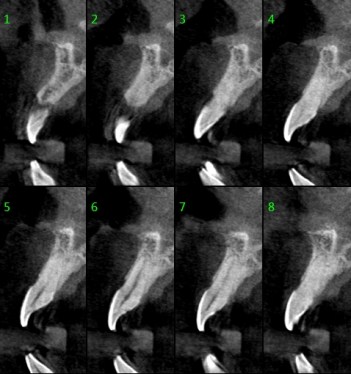

Great Quality ImagesAdopt 3D reconstruction algorithm. |